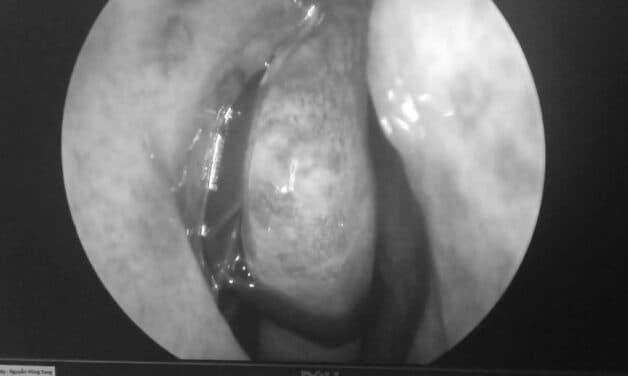

Hình ảnh vắt trong hốc mũi thanh niên sau chuyến phượt (Ảnh: Báo Người lao động)